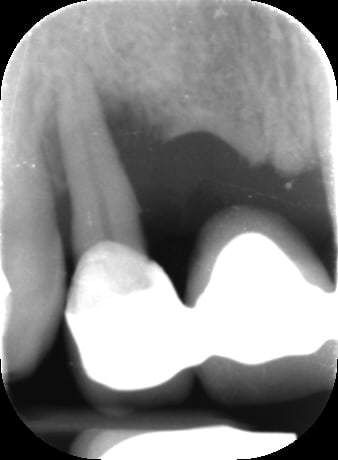

Bon voila le scann de 11-12 (pas 21-22 comme noté)

C'est vrai que j'ai à mort d'os en épaisseur.

Le manque est surtout en hauteur.

Dans tous les cas je refais 21 en même temps.

Tu ne ferais qu'un conjonctif enfoui ? Tu crois que c'est fiable dans le temps ?

j'ai l'impression qu'il ne manque pas d'os en verticale, ou à peine en 12.

Un bon cj avec un lambeau décalé en palatin ou en rouleau pour gagner en épaisseur me semblerai suffisant

le montage guide RX laisse supposer un manque d'un mm en 12 et ok en 11. Surcomble en cj pour en éliminer au cas où avant les empreintes